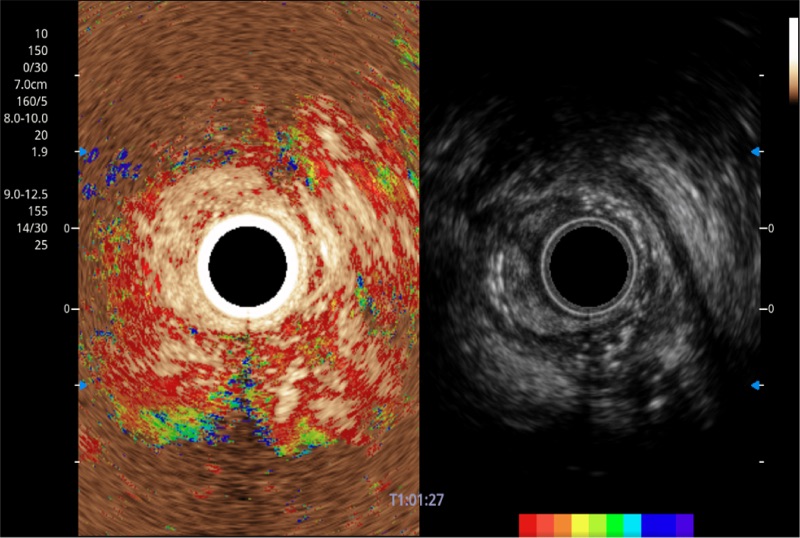

可人為將灰階圖像轉(zhuǎn)變成彩色的顯示方式,增強(qiáng)人眼對(duì)于不同回聲強(qiáng)度的敏感度,主觀上增加了圖像分辨率

TIC時(shí)間強(qiáng)度分析曲線

具有四種造影成像效果